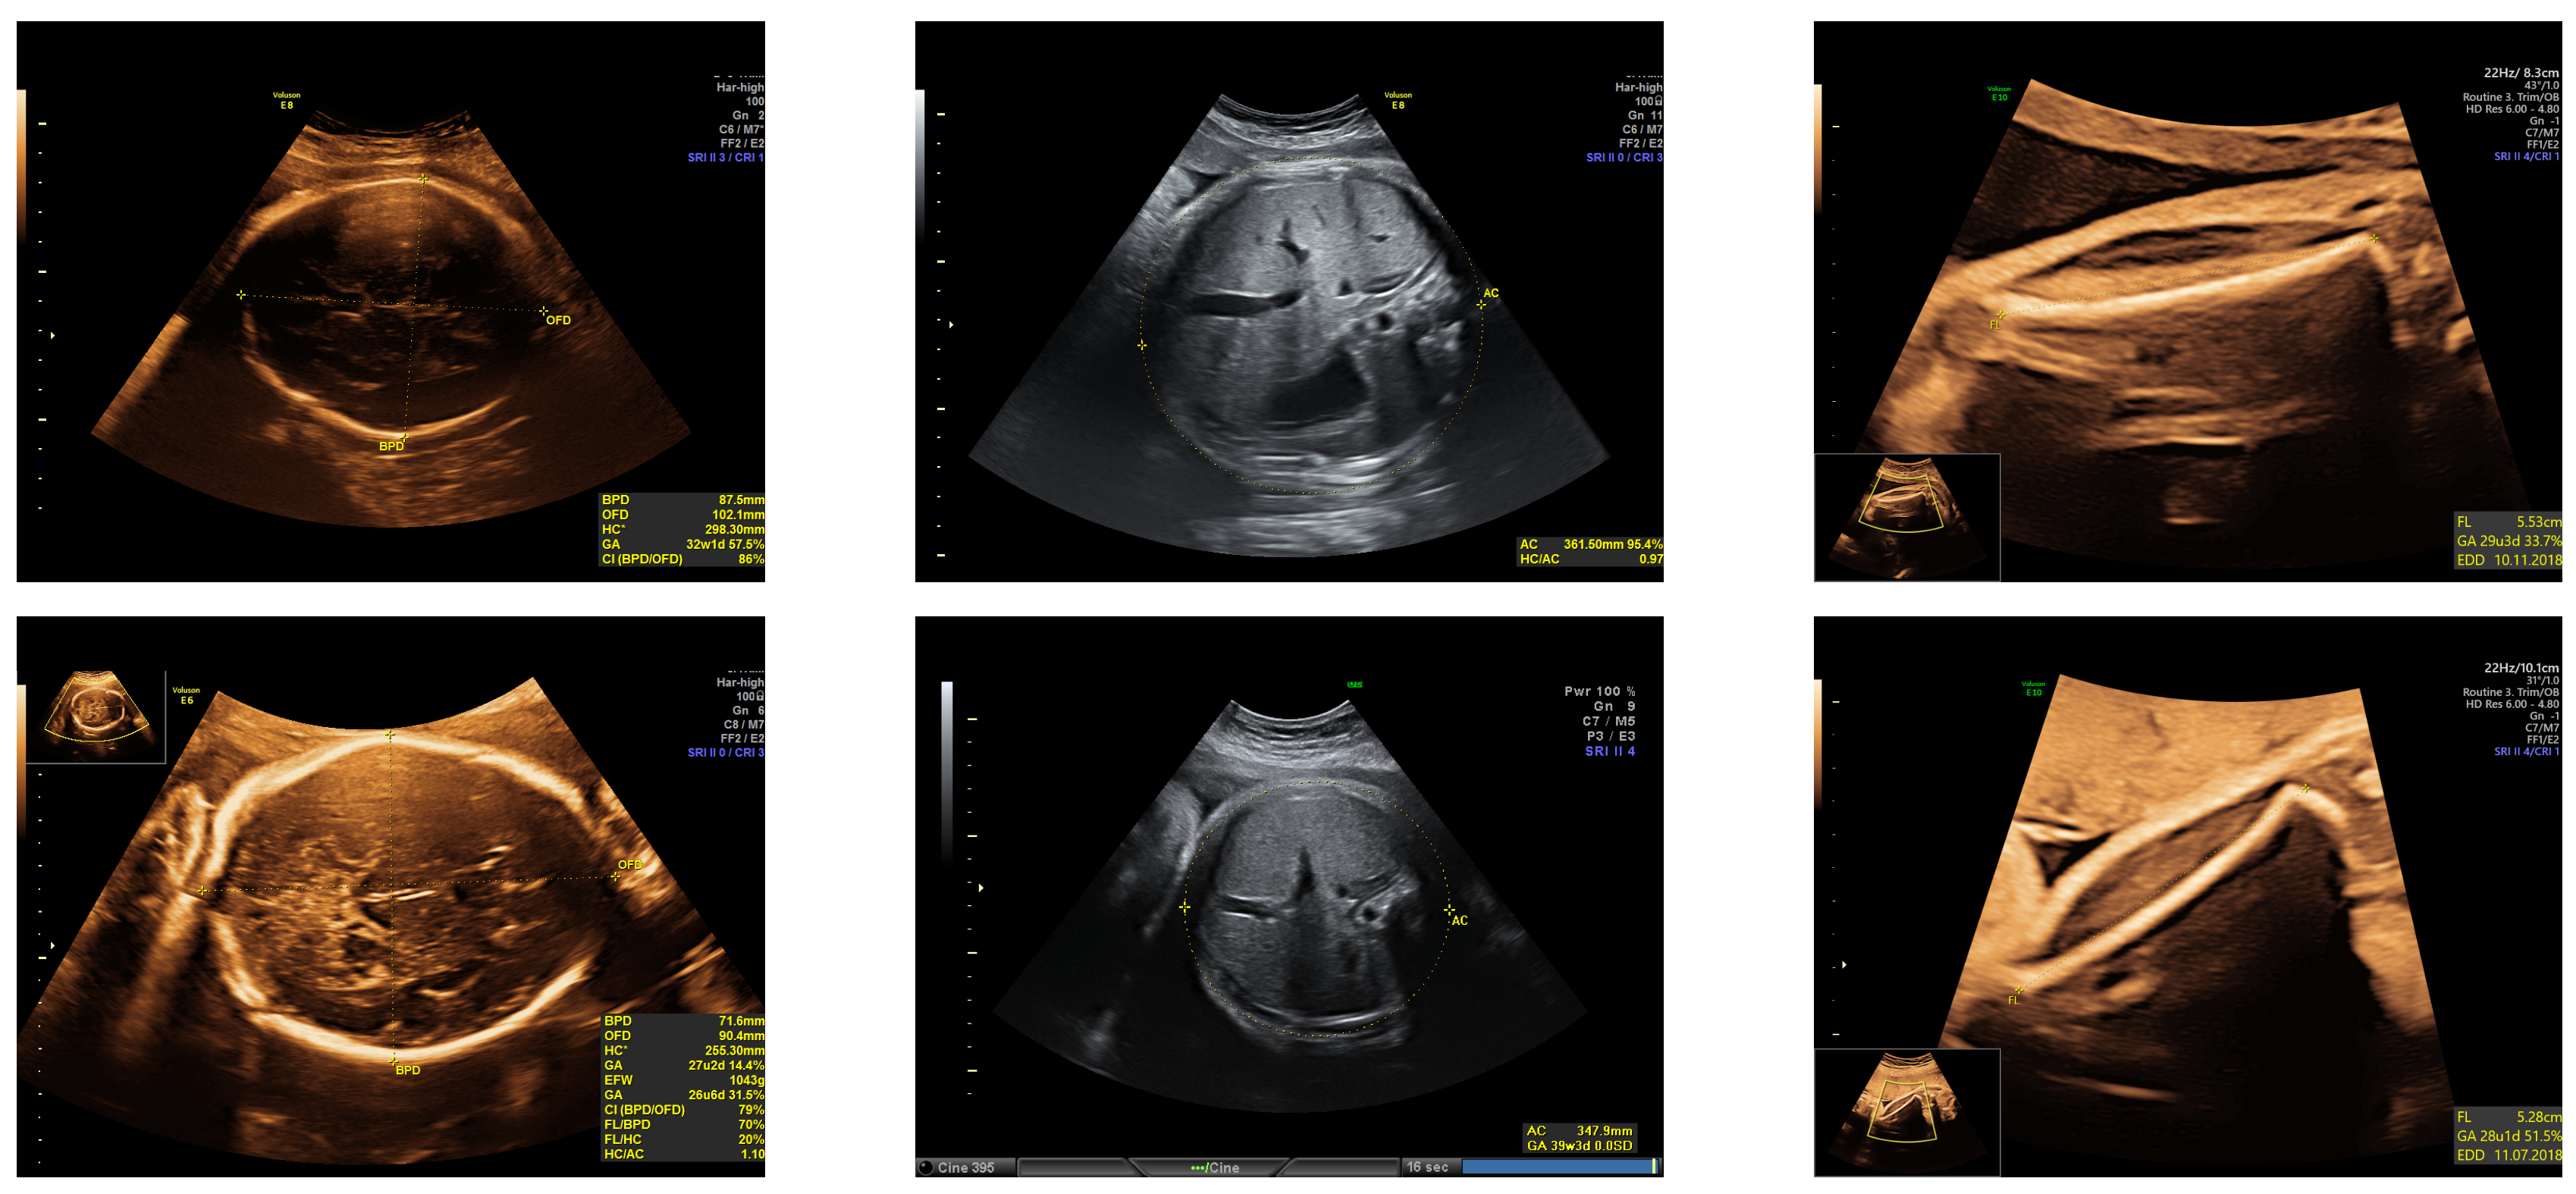

Clinical data is a great potential source of data for training medical imaging models: It can come in vast amounts, and represents the nature of data quality encountered in clinical practice. However, when data comes from the clinic, there is little control of the data generating process, and the data may be affected in ways that are suboptimal for training deep learning models. In particular, clinical images sometimes come with embedded text, markings, calipers or other annotations made by the clinician, and these likely carry information correlating with the predictive task at hand. It has recently been shown that markings, stickers and rulers present in dermatological images can confound predictors that aim to diagnose skin lesions [6, 12, 7]. In this paper, we consider confounding information present in fetal ultrasound images from clinical screening. As shown in Fig. 1, these images often have text and calipers embedded in them, which can affect predictors trained on the images. As a case study, we use standard plane classification, which aims to automatically recognize those ultrasound planes required for particular types of screening tests during pregnancy.

Refer to caption

Figure 1: Examples of clinical ultrasound images with text and calipers, i.e. annotated coordinates for measuring anatomical objects, embedded into the image. Note that both the text labels and the caliper geometry carries information about the particular standard plane that the image contains.